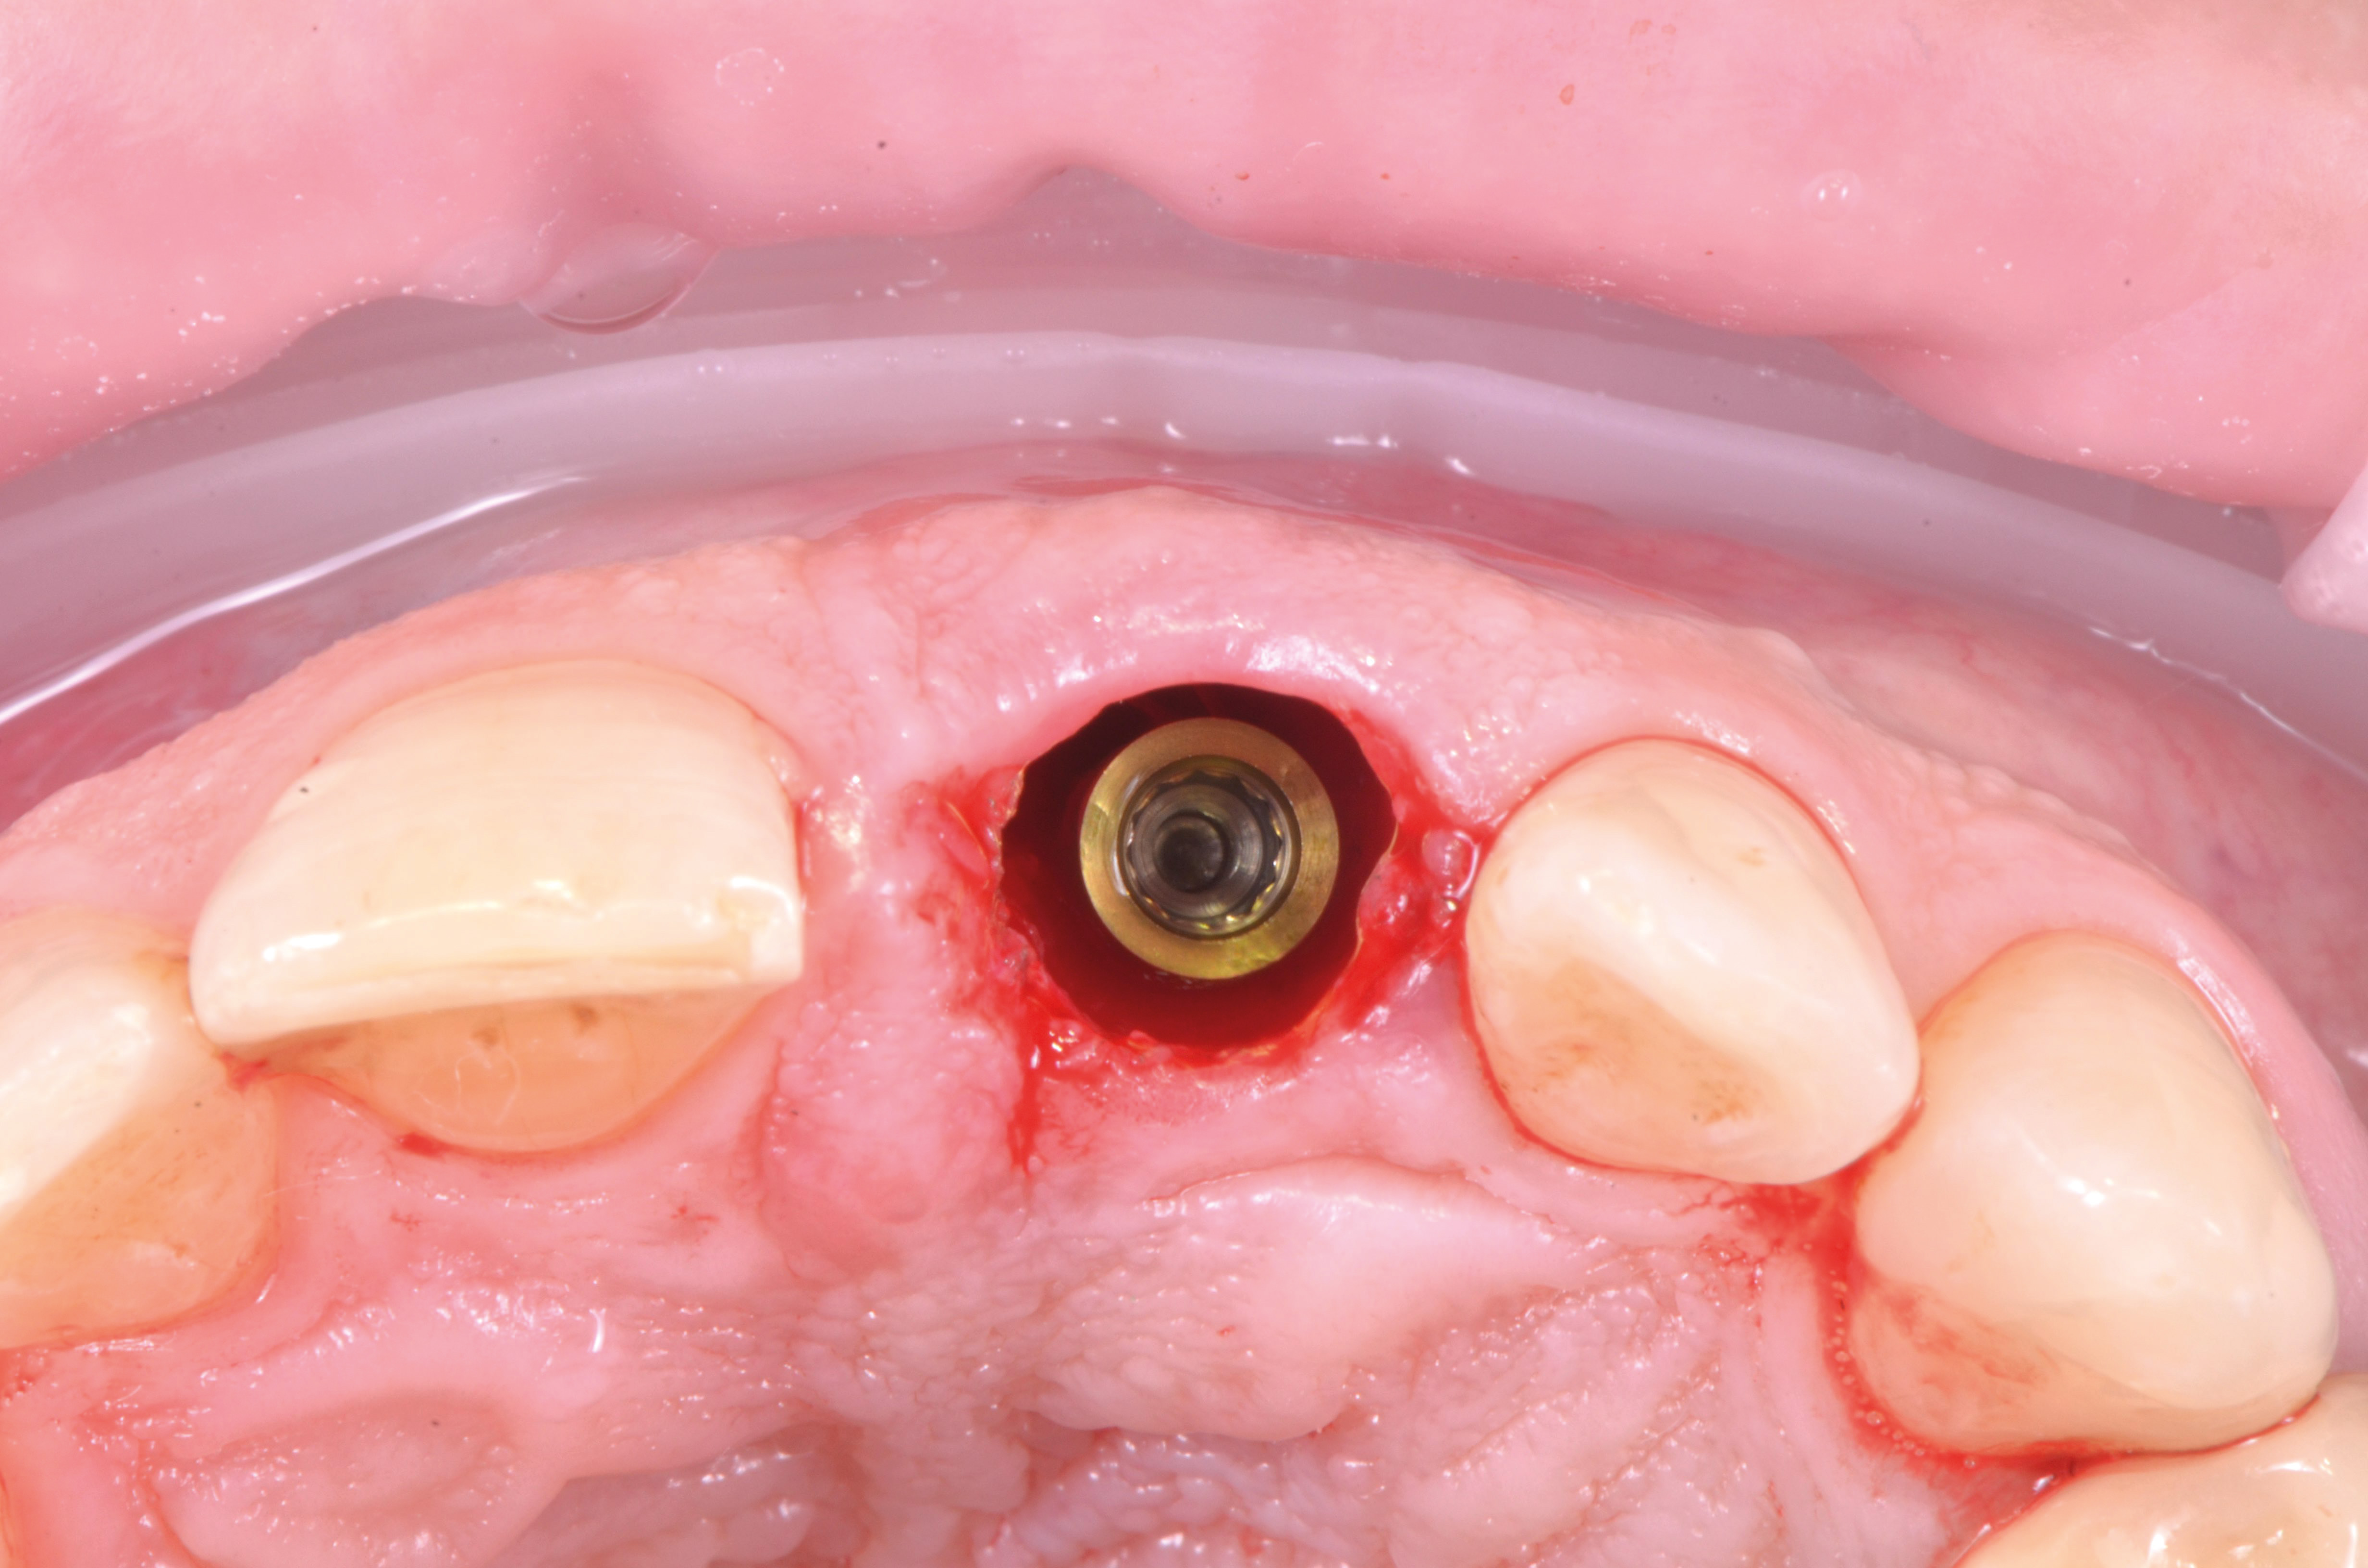

Una volta posizionata la dima chirurgica si è eseguita l’osteotomia guidata con frese a diametro crescente ed è stato posizionato l’impianto (MIS V3, MIS Implants ltd global, Bar Lev, Israele)(fig.7,8).

Seguendo le indicazioni del progetto chirurgico/protesico è stato posizionato un pilastro intermedio in titanio anodizzato (MIS Connect, MIS Implants ltd global, Bar Lev, Israele) con la tecnica del “one-abutment-one-time” con lo scopo di spiazzare la connessione protesica in una posizione più coronale (fig.9).